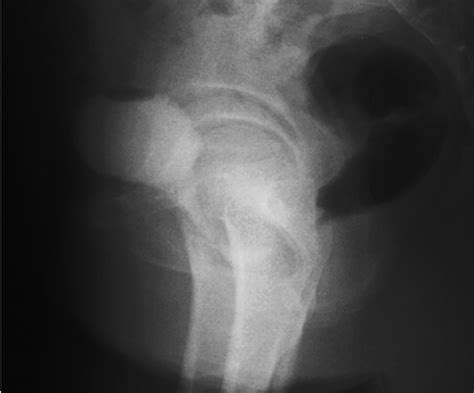

MRI (Magnetic Resonance Imaging) The gold standard for visualizing the size and location of the diverticulum.

Voiding Cystourethrogram (VCUG) Uses contrast dye to see if the pouch fills during urination.